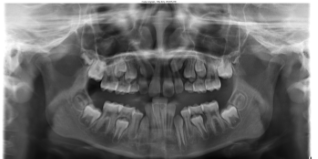

| Severe Crowding | The permanent teeth do not have enough room to erupt (come through the gums) where they belong. | ![]() | Monitored extraction (removal) of baby teeth and possibly some permanent teeth. |